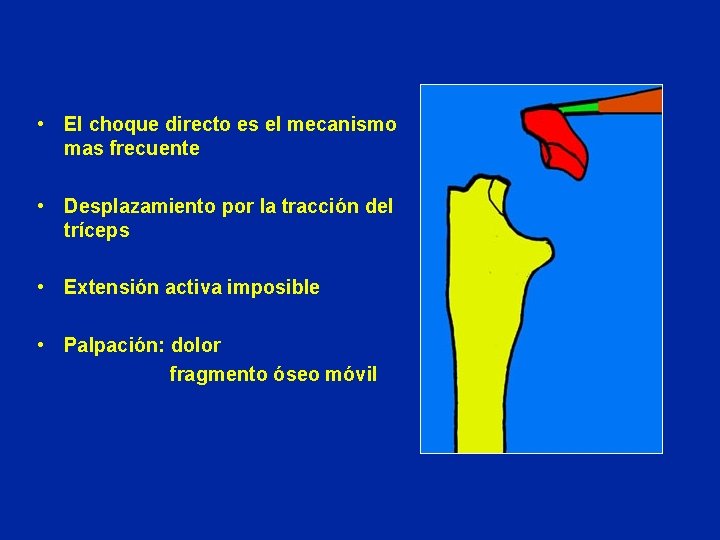

• El choque directo es el mecanismo mas frecuente • Desplazamiento por la tracción del tríceps • Extensión activa imposible • Palpación: dolor fragmento óseo móvil